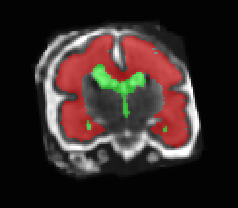

Limiting failures of machine learning systems is of paramount importance for safety-critical applications. In order to improve the robustness of machine learning systems, Distributionally Robust Optimization (DRO) has been proposed as a generalization of Empirical Risk Minimization (ERM). However, its use in deep learning has been severely restricted due to the relative inefficiency of the optimizers available for DRO in comparison to the wide-spread variants of Stochastic Gradient Descent (SGD) optimizers for ERM. We propose SGD with hardness weighted sampling, a principled and efficient optimization method for DRO in machine learning that is particularly suited in the context of deep learning. Similar to a hard example mining strategy in practice, the proposed algorithm is straightforward to implement and computationally as efficient as SGD-based optimizers used for deep learning, requiring minimal overhead computation. In contrast to typical ad hoc hard mining approaches, we prove the convergence of our DRO algorithm for over-parameterized deep learning networks with ReLU activation and a finite number of layers and parameters. Our experiments on fetal brain 3D MRI segmentation and brain tumor segmentation in MRI demonstrate the feasibility and the usefulness of our approach. Using our hardness weighted sampling for training a state-of-the-art deep learning pipeline leads to improved robustness to anatomical variabilities in automatic fetal brain 3D MRI segmentation using deep learning and to improved robustness to the image protocol variations in brain tumor segmentation. Our code is available at https://github.com/LucasFidon/HardnessWeightedSampler.